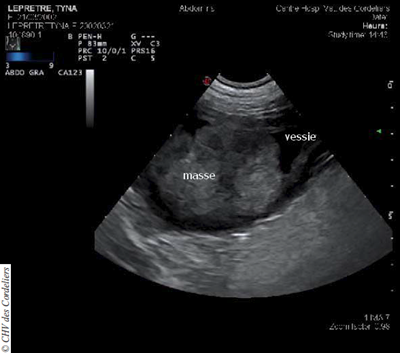

À l’examen échographique abdominal, une volumineuse masse d’aspect hétérogène et d’échogénicité principalement tissulaire est visualisée à l’apex de la vessie (photo 1), elle est déstructurante pour la paroi à sa zone de naissance. La vessie est ponctionnée par cystocentèse : la bandelette urinaire montre la présence de sang et de protéines en quantités importantes et l’examen cytologique du culot n’apporte pas de résultat significatif.

Photo 1 : Volumineuse masse vésicale d’aspect hétérogène.